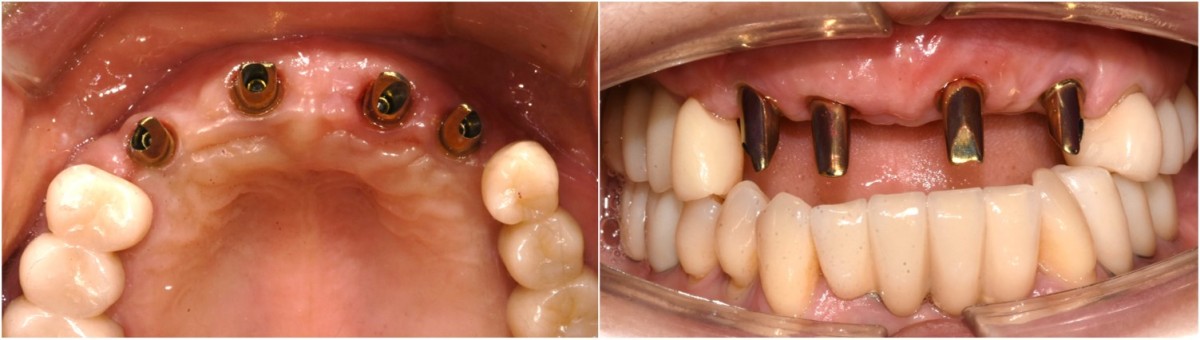

Anterior implant placement with Arum implant system in the maxilla.

▲Fixture to be placed. Arum® implant NB1

▲Implant placement GBR